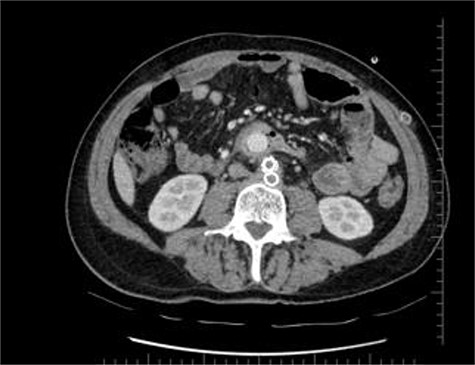

Coronal CT section shows straight part of the Dacron graft in the jejenum.

During the first days of December 2018, the patient visited another medical center because of fatigue, difficulty in breathing, lower back pain and inability to walk. His blood biochemistry revealed a very high CRP level (350 mg/dl), and complete blood count revealed a very high level of white blood cells (21 000/ul). An abdominal CT scan illustrated part of the graft was totally eroded into the small intestine (Figs 1–3). The patient was referred to my office and an infectious disease specialist. He had high body temperature (39.5°C) and was lying on the bed with lower extremities adducted to the chest. Antibiotic and supportive treatment was started. Emergency surgery was performed. We found an 8–10 cm of the straight part of the graft had become totally incorporated into the proximal part of the jejenum. The graft was freed, and 10–15 cm of the jejenum was resected and anastomosed. The area was irrigated with saline and hypochlorous acid. We then put a 20 x 10 composite mesh between the vascular graft and the intestine using a non-adhensive surface facing the intestine to prevent future graft and intestine interactions and erosion. After hemostasis, two drains were placed retroperitonally, and the abdomen was closed. On the fourth post-operative day, a high body temperature and high CRP levels were recorded. An abdominal CT revealed retroperitoneal abcess formation. During relaparotomy, the anastomosis was found to be intact, and the retroperitoneal abscess was drained and irrigated with saline. The drains were reinserted. After a month, he once again started to have high fever and high CRP levels. Again, an abdominal CT revealed abscess formation. This time, the abscess was approached transcutaneously. By making an incision in the proximal left lomber region, the abscess was drained. Another incision was made distally, and two drains were placed in the retroperitoneal area.